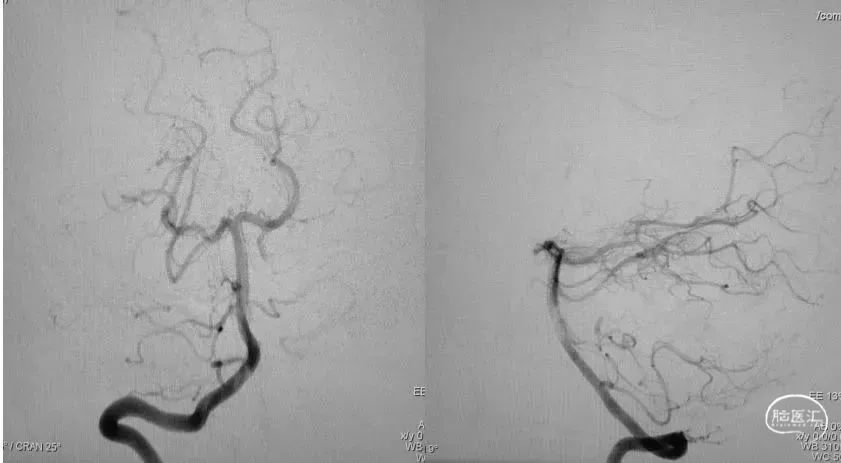

DSA提示:右侧大脑中动脉M1段以远闭塞,右侧大脑前动脉皮层支少量代偿,右侧大脑前动脉A3段血栓影,远端流速可,基底动脉尖端未见显影,考虑急性闭塞。

造影提示右侧大脑中动脉血流通畅。

复查造影示基底动脉及其分支显影良好,取栓装置中可见白色胶冻状血栓。

神志清楚,言语流利,双侧瞳孔等大等圆,直径3.0mm,对光反射灵敏,左侧鼻唇沟浅。左侧肢体肌力3级,右侧肢体肌力5级,双侧病理征阴性。感觉、共济查体未见异常,脑膜刺激征(-)。

NIHSS评分:5分。

神志清楚,言语流利,双侧瞳孔等大等圆,直径3.0mm,对光反射灵敏,左侧鼻唇沟浅。左侧肢体肌力4级,右侧肢体肌力5级,双侧病理征阴性。感觉、共济查体未见异常,脑膜刺激征(-)。

NIHSS评分:3分。